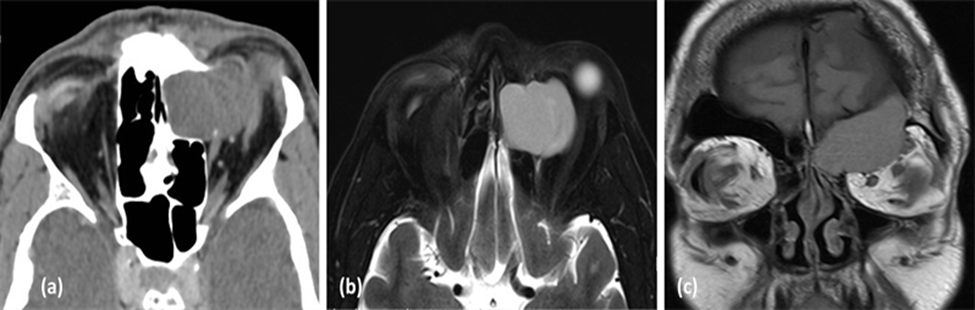

Hình ảnh lâm sàng và MRI của 1 bệnh nhân u nhầy xoang sàng, có biến chứng lồi mắt- Được chẩn đoán và điều trị phẫu thuật tại bệnh viện đa khoa tỉnh Quảng Trị

Hình ảnh lâm sàng và MRI của 1 bệnh nhân u nhầy xoang sàng, có biến chứng lồi mắt

- Được chẩn đoán và điều trị phẫu thuật tại bệnh viện đa khoa tỉnh Quảng Trị

(a) Hình ảnh CT scan lát cắt axial cho thấy u nhầy xoang trán- sàng trái gây tiêu xương thành trong ổ mắt trái và (b) Hình ảnh MRI lát cắt axial và (c) nhát cắt coronal trên cùng 1 bệnh nhân cho thấy hình ảnh xâm lấn vào ổ mắt, gây ra trên lâm sàng bệnh nhân có lồi mắt trái. (Nguồn: Sarah A. AlMansour1, Ali A. AlMomen2 The Endonasal Endoscopic Management of Paranasal Sinuses Mucoceles (2021))